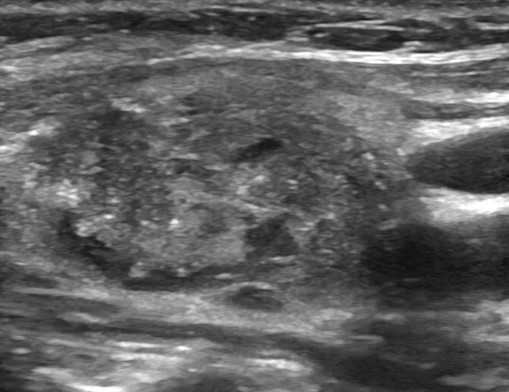

Образования, узлы. Во время сканирования доктор оценивает очаговую патологию и делает заключение в предположительном ключе. УЗИ щитовидной железы показывает:

Дифференциация опирается не только на серошкальные изображения, но и на данные ЦДК.

В пользу доброкачественности узлов свидетельствует совокупность признаков:

- изо-, гипоэхогенность;

- правильность формы;

- ровность, четкость контуров;

- превалирование длины над высотой;

- размеры менее 1 см;

- отсутствие кровотока.

Рак щитовидной железы на сонограммах имеет:

- неоднородную преимущественно гипоэхогенную структуру,

- неправильную форму;

- размеры свыше 1 см - новообразования более 4 см всегда подозрительны на малигнизацию;

- множественные кисты/узлы, участки отложения кальция, фиброз;

- рваные, размытые контуры.